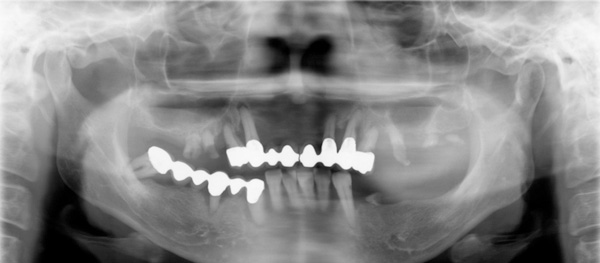

患者さんは40歳代の女性 重度の歯周病です。歯の本数が少なくなり噛み合わせを維持することができなくなる咬合崩壊がおこってます。そのために崩壊した噛み合わせを出来るだけ崩壊以前の元の状態にもどす咬合再構成が必要になります。フィスボウトランスファー(必要ないという先生もいますが、その人の咬み合わせを再現するときとても重要な診査です)をおこない、仮の適正な咬み合わせ(中止位)を咬合器(咬み合わせを再現させる装置)で再現し、理想的な咬み合わせのゴールを設定し(診断用ワックスアップ)、プロビジョナルレストレーション(治療用の仮歯)に置き換えていきます。それに合わせた位置にインプラントを入れていく必要があります。インプラント治療は目的でなく手段です。そして可能な限り天然歯(自分の歯)を残す歯周病の治療を行います。

初診時

フェイスボウトランスファーをおこない、中心位で咬合器につけました。咬合診断し、ポイントは咬み合わせの低下がみられたので、3㎜高くしました。